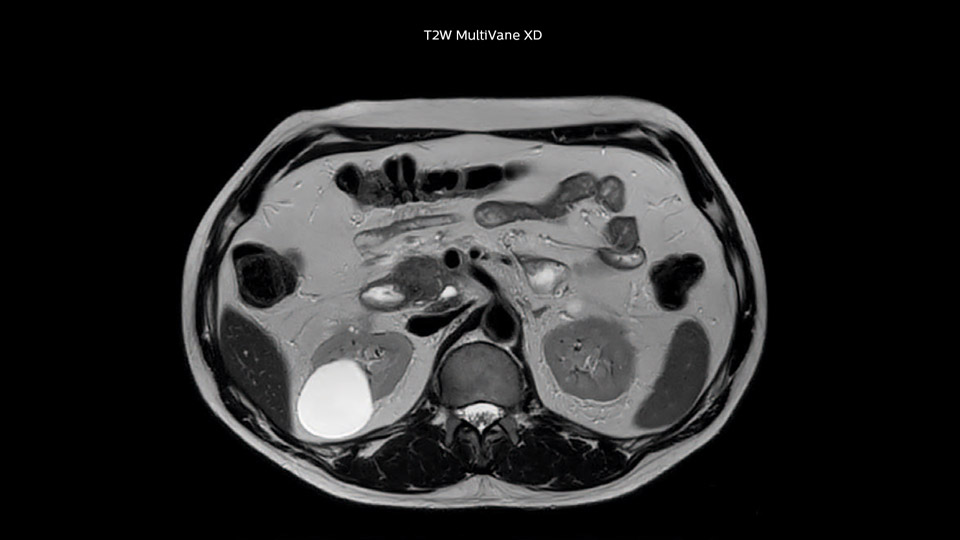

“Our liver exams are quite fast,” says Dr. Baumann. “If the patient tolerates it, we use an arms-up position to reduce the FOV and speed up the exam with dS SENSE.” “We acquire one transversal high resolution T2-weighted sequence with 3 mm slice thickness, for example for pancreas or liver lesions. Then we also add a T2 fat suppressed MultiVane XD SPIR sequence. We perform these two routinely in our liver imaging. We use high dS SENSE factors to significantly shorten scan times to 2-4 minutes, which can improve our protocol; it’s a very robust scan.” “We include mDIXON for the dynamic sequences because of the robust and homogeneous fat suppression we get with that. We had been using eTHRIVE, but we are now quite happy with mDIXON. Sometimes we use a medication to calm the bowels, to further improve the image quality.”

Dr. Baumann then implemented MultiVane XD for motion correction. It uses an extended reconstruction algorithm for imaging that is virtually motion free. “With MultiVane XD we get excellent motion-corrected images with high spatial resolution. We typically first optimize our scan for high image quality, and when satisfied with that, we try to reduce the scan time. So, we combined MultiVane XD with dS SENSE, which allows us to shorten the scan time,” he explains. “The performance of MultiVane XD in liver imaging is outstanding. MultiVane XD with dS SENSE is a powerful development in improving liver image quality.” “As we use breathhold imaging for T2-weighted liver scans, we depend on the patient’s ability to cooperate with the exam. This can present a real challenge when we are looking for small lesions, such as in our oncological patients. However, with MultiVane XD motion correction, we get excellent images. This is important for our surgeons, because they want to know exactly where the lesions are.”